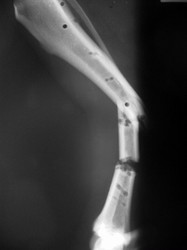

Fijación Externa

PRÁCTICAS CURSO DE FIJACIÓN EXTERNA PERFECCIONAMIENTO.

Híbrido.